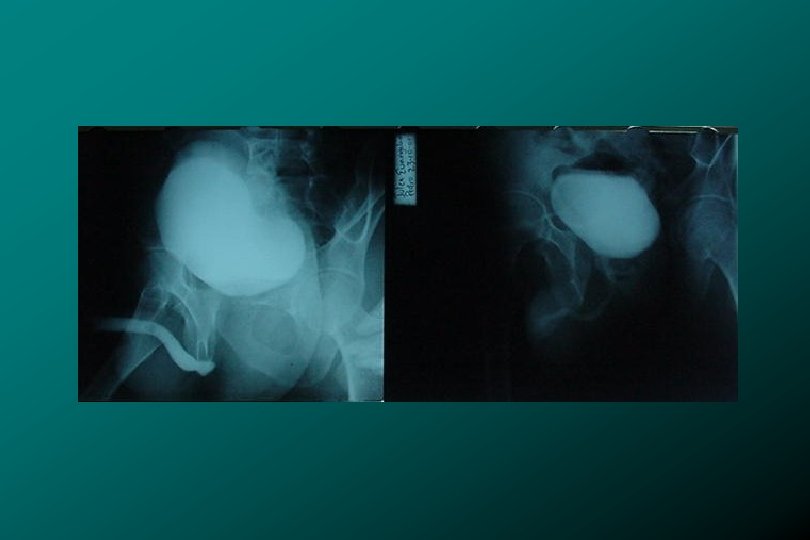

TRAUMA DE URETRA POSTERIOR CLASIFICACIÓN * Tipo II Ruptura uretra prostatomembranosa (17%). * Zegarra

TRAUMA DE URETRA POSTERIOR CLASIFICACIÓN * Tipo II Ruptura uretra prostatomembranosa (17%). * Zegarra L. : Traumatismos Urológicos. En: Barboza ed. Principios y Terapéutica Quirúrgica. Lima: De Arteta Imp. 1999: 576 -590.